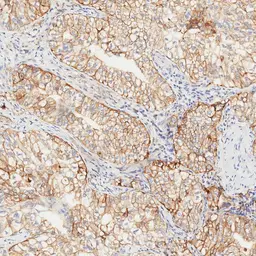

Optimal staining result of human NSCLC, tissue core no. 6, using PD-L1 antibody [H302] HistoMAX™ on Leica Bond III, following the vendor recommended protocol settings.

Distinct membranous reactivity ranging from weak to strong intensity is demonstrated across virtually all tumor cells. Based on this diffuse expression pattern, the tumor is categorized as TPS High (≥50%).